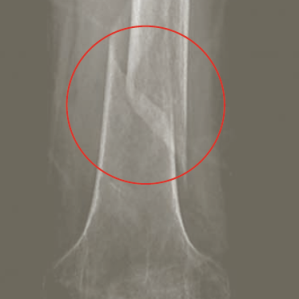

Osteoporosa (dal grec «oss» e «dir») è ina reducziun exagerada da la substanza e structura da l’ossa da l’entir skelet. En ospitals svizzers vegnan tractads, tenor la Osteoswiss, mintg’onn radund 26 000 pazientas e pazients cun ruttadiras da l’ossa pervi d’osteoporosa. Da l’osteoporosa èn pertutgadas per la gronda part dunnas e persunas sur 40. Ils motivs èn differents: disposiziun genetica, mancanza d’ormons sexuals (tar dunnas savens suenter la menopausa), nutriment manglus, funcziuns falladas da las glondas tiroidas u anorexia. Tenor l’Organisaziun mundiala da la sanadad WHO vegn l’osteoporosa considerada sco ina da las diesch malsognas las pli frequentas en l’entir mund e valitada sco in dals problems da sanadad principals.